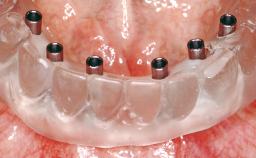

Conventional Loading of Eight Implants in the Maxilla and Final Restoration with a Full-Arch Gold-Ceramic FDP

# of Implants 8

Type of Implants One-Piece

Defining Characteristics Fully edentulous upper jaw to be rehabilitated with four or more implants

Modality Fixed hybrid bridge on 5+ implants